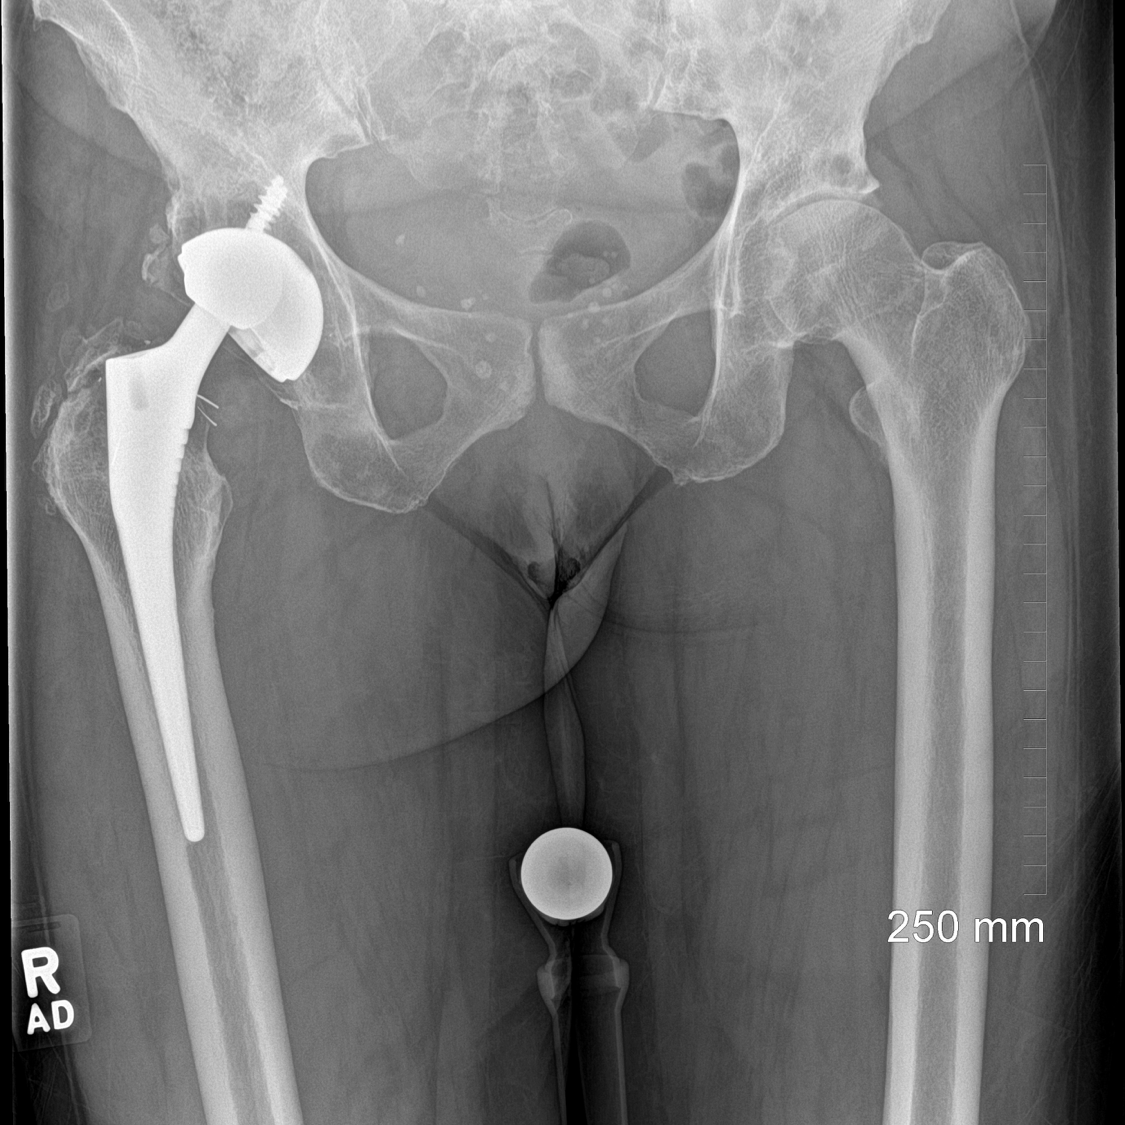

Anteroposterior plain radiograph demonstrating a cracked right polyethylene liner within a titanium shell. The head is bearing onto the titanium shell.

Anteroposterior plain radiograph of the pelvis demonstrating the bilateral revision with acetabular bone graft on the right hand side.

Lateral plain radiographs of the pelvis demonstrating the jumbo acetabular cup in situ with a long Restoration stem.